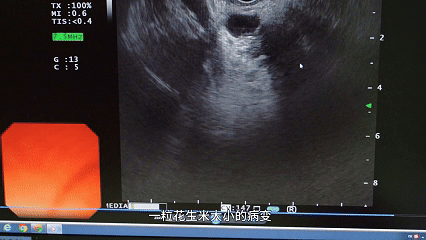

但 EUS(超声内镜)这位「超级侦探」,专门破解这个难题→

医生打了个形象的比方:「胰腺躲在胃后面,就像抽屉最里层的秘密文件。普通 B 超只能在门口张望,而超声内镜能直接拉开抽屉,用毫米级探头『贴脸』扫描。」 1 粒花生米大小(10 mm)的病变,CT 可能漏诊,EUS 却能精准锁定。

EUS 不仅能「侦察」,还能「治疗」:胰腺囊肿穿刺引流、肝硬化患者胃底静脉曲张出血止血、放支架解除胆道或十二指肠梗阻…… 早期发现的小胰腺癌,用它筛查后做微创手术,5 年生存率能超 80%~